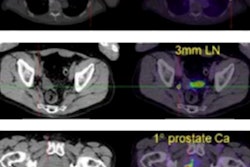

Prostate-specific membrane antigen (PSMA)-PET/CT imaging is comparable to MRI for detecting clinically significant prostate cancer. But MRI is still the more accurate modality for detecting the grade of disease, according to research presented on 3 July at the annual congress of the European Association of Urology (EAU) in Amsterdam.

Although PSMA-PET/CT imaging found more abnormalities than MRI exams did, MRI was more accurate in identifying the grade of prostate cancer than PSMA-PET/CT, at 75% compared with 62%, the team noted. But the two modalities were comparable when it came to identifying clinically significant prostate cancer, Wong noted.